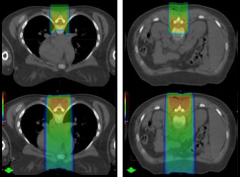

质子治疗颅底脊索瘤和软骨肉瘤

脊索瘤是一种少见的低度恶性肿瘤,常发生于斜坡区。由于转移...